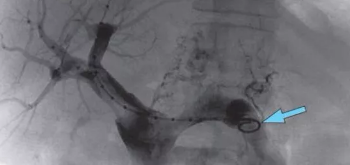

肝硬化腹水是一种慢性肝病,由大块型、结节型、弥漫型的肝细胞坏死、再生,促使组织纤维增生和瘢痕的收缩,致使肝质变硬,形成肝硬化。肝硬化后肝功能减退引起门静脉高压,导致脾肿大,对蛋白质和维生素的不吸收而渗漏出的蛋白液,形成了腹水症。

肝硬化可以出现腹水,但肝硬化不等于腹水,腹水的出现,提示肝脏功能已进入失代偿状态和门静脉高压症的存在。